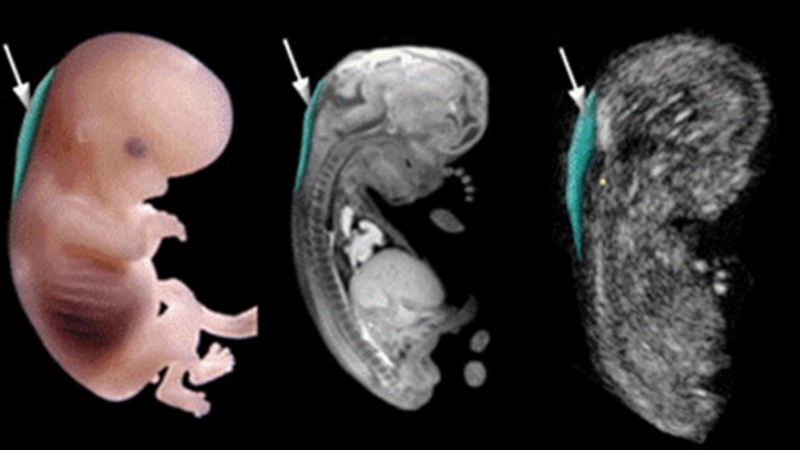

Siêu âm nhiều có ảnh hưởng đến thai nhi không?

Siêu âm là phương pháp giúp theo dõi sự phát triển của thai nhi khi còn trong bụng mẹ. Tuy nhiên nhiều mẹ bầu lo lắng rằng không biết siêu âm nhiều có ảnh hưởng đến thai nhi không? Hãy cùng tìm hiểu về vấn đề này với nhà thuốc Long Châu qua bài viết dưới đây nhé

Lúc này thai nhi đã tăng trưởng hoàn thiện các bộ phận cơ thể nên có thể trông thấy rõ hình thái thai nhi và xác định sớm các dị tật ở thai nhi ví như có như thiếu ngón tay, chân, hở hàm ếch,...